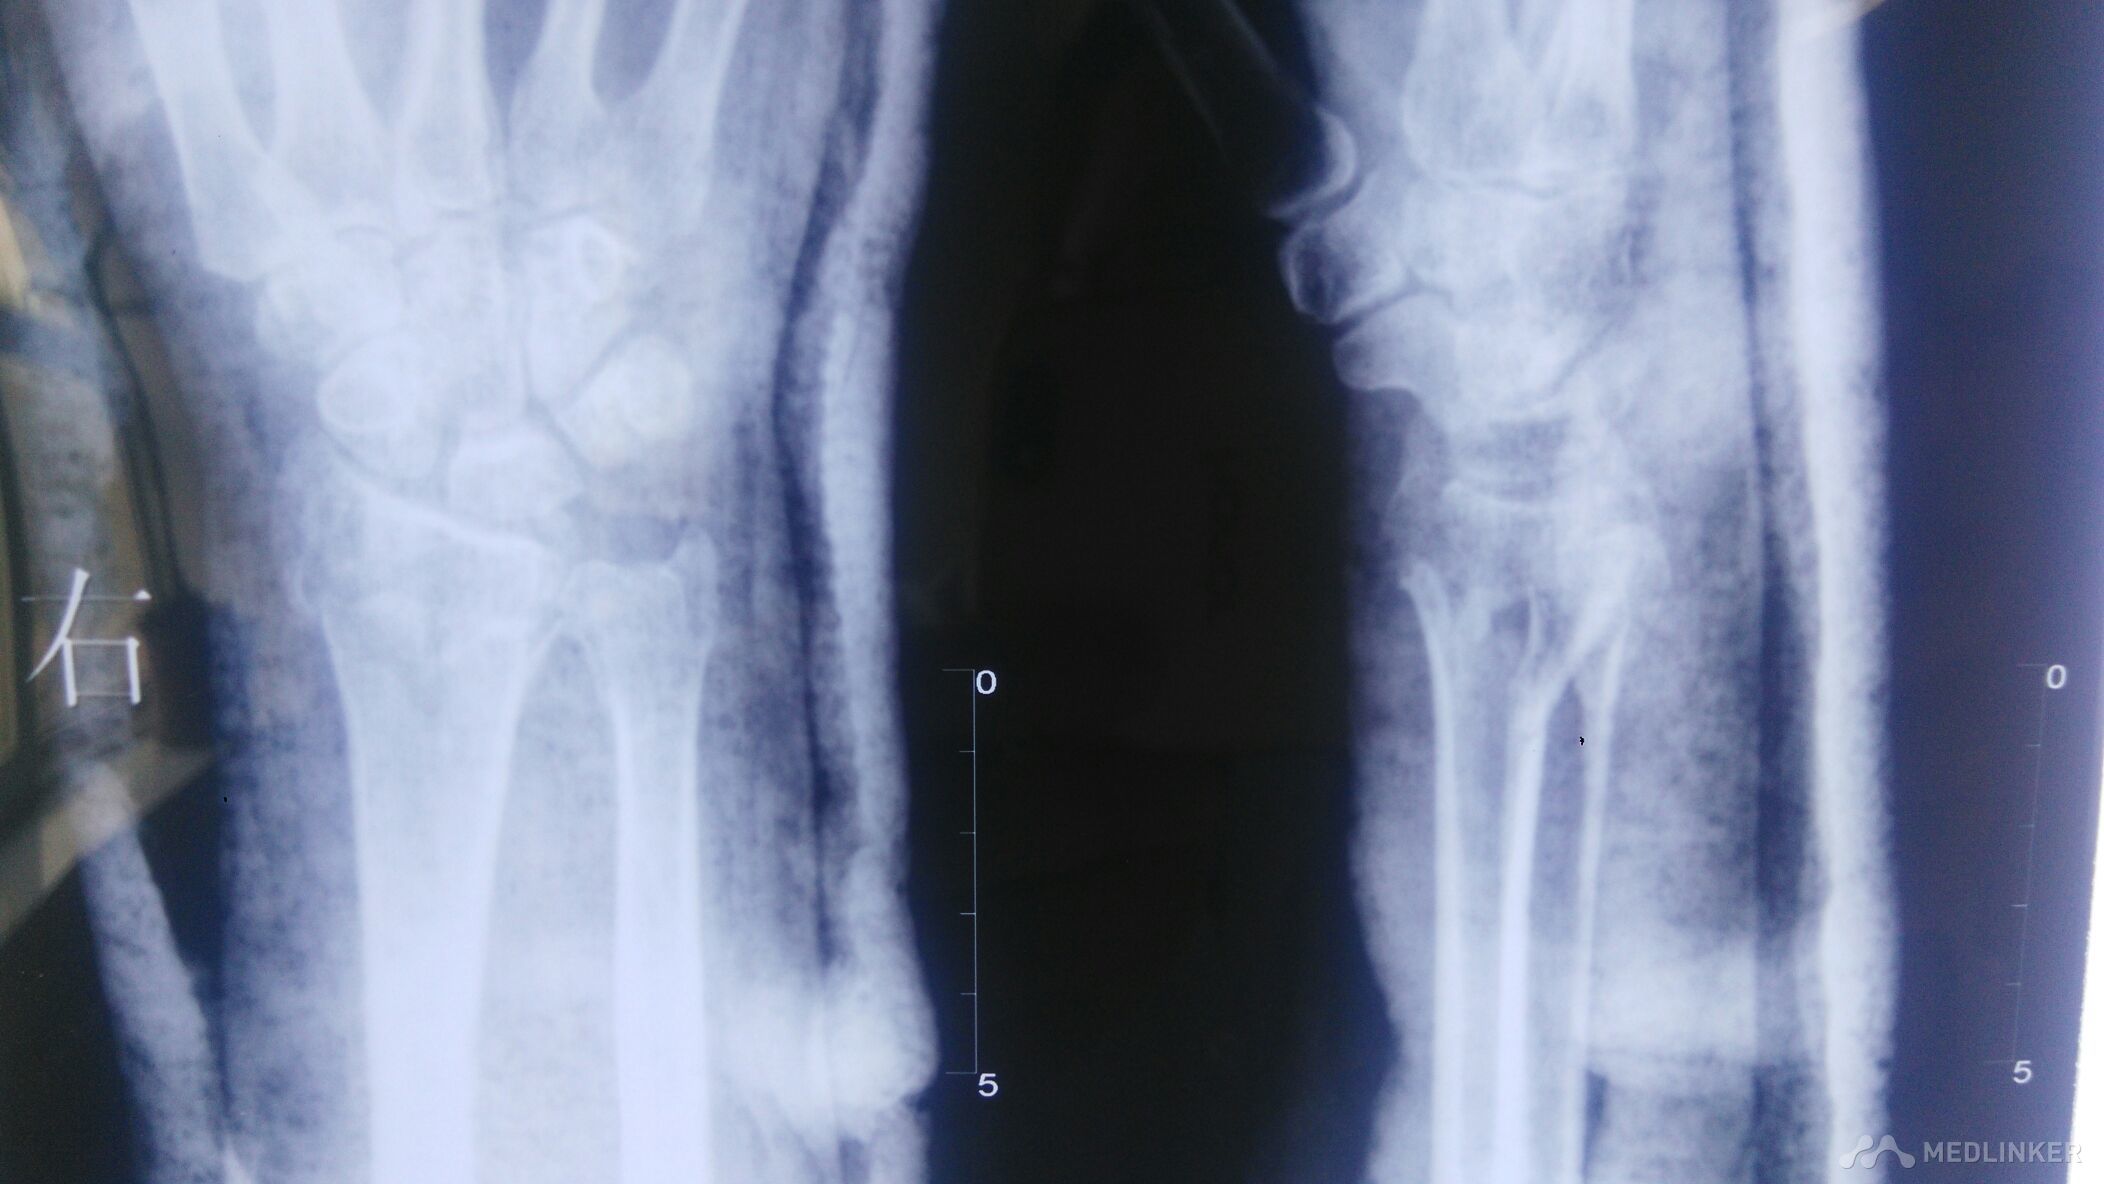

右腕部外伤后,畸形明显,肿胀明显。右腕部感觉麻木。活动受限。

右腕部以桡骨远端处,尺骨远端处压痛阳性,叩痛阳性,右手血运可。末梢冰冷。

右侧桡骨远端粉碎性骨折,右侧尺骨远端骨折,保守治疗。

畸形明显,肿胀明显,复位,就和时间赛跑。尽力就有希望,不要放弃保守治疗的机会。